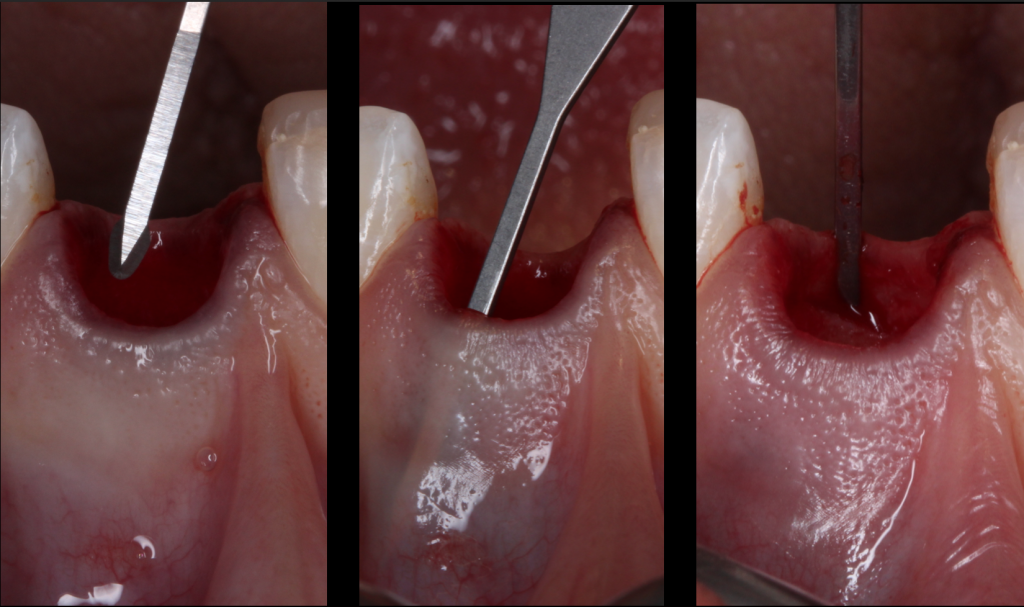

#3. The soft tissue punch technique

The soft tissue punch (Landsberg and Bichacho, 1994) (Jung et al., 2004) is removed from the palate or from the maxillary tuberosity.

The tuberosity sampling makes it possible to obtain a greater graft thickness and a lower post-operative sensitivity. However the tissue is more fibrous is less vascularized which can hinder its healing.

A palatal sample is therefore recommended: it is performed with the knife blade (No15, 15 C) or with a circular knife provided for this purpose.

The protection of the sampling site is identical to an epithelial-connective sampling technique with a hemostatic material and fixation sutures.

The punch is positioned directly in contact with the biomaterial, so its vascular supply is very low and the morbidity of this therapy is high (Thalmair et al., 2010).

The principles of this technique are :

- Atraumatic extraction with preservation of the marginal periodontium

- Suppression of the sulcular epithelium with the diamond bur or the scalpel blade to increase the vascular supply

- Removal of almost the entire thickness of the palate

- Punch size slightly higher than the recipient site

- Adaptation and immobilization of the punch with several simple points

- Tissue maturation is about 3 months (Thalmair et al., 2013).